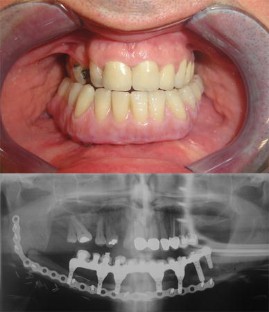

At present, mandibular reconstruction with a fibular free flap is the gold standard for functional and esthetic rehabilitation after oncological surgery. The purpose of this study was to describe the computer-assisted mandibular reconstruction procedure adopting the customized solution Synthes ProPlan CMF. The study reports five consecutive patients with benign or malignant disease requiring mandibular reconstruction using a microvascular fibular free flap, pre-operative virtual planning, construction of cutting guides and customized laser pre-bent titanium plates. The surgical technique is discussed in a step-by-step fashion. The average post-operative hospital stay was 18 ± 3 days. Ischemia time was recorded in all five cases, with an average of 75 ± 8 min. No problems were encountered in any surgical step and there were no major complications. Excellent precision of cutting guides and a good fit of pre-bent plates were found on both the mandible and fibula. There was excellent precision in bone to bone contact and position between mandible and fibula graft. Measurement data from the pre-operative and post-operative CT scans were compared. The average difference (Δ) between programed segment lengths and CT control segment lengths was 0.098 ± 0.077 cm. Microsurgical mandibular reconstruction using a virtual surgical planning yields significantly shorter ischemia times and allows more precise osteotomies. The technology is becoming increasingly recognized for its ability to optimize surgical outcomes and minimize operating time. Considering that the extent of resection can be wider than predicted, this results in safer modeling of the fibula only after frozen sections have demonstrated the radicality of resection.